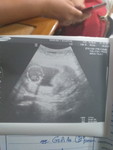

ตอนท้องลูกผู้ชายไม่แพ้แต่ท้องนีแพ้หนักมากมีแววจะเป็นผู้หญิงมัยค่ะ

มีแววจะได้ผู้หญิงมัย